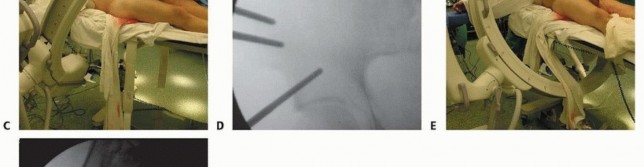

This requires that the drill be held more cephalad (directed caudad) than expected to allow proper position within the desired supra-acetabular bone (superior and cephalad to the acetabulum) rather than the thin bone of the ilium. Triple cannulated drill sleeves are used to protect soft tissues. The fixation pin is inserted, allowing the cortical walls of the ilium to establish direction. An image intensifier may aid in elective nonemergent fixator application. 2. ## Supra-acetabular Technique The patient is positioned supine on a radiolucent table. Safe introduction and proper positioning of the pin require the assistance of fluoroscopic guidance. The open approach for pin placement begins with a vertically oriented 5- to 10-cm incision, depending on patient body habitus and prereduction pelvic deformity. A smaller transverse incision has been described in addition to entirely percutaneous techniques of pin insertion. This vertical approach begins along the lateral border of the anterior superior iliac spine, extending distally and lateral to the AIIS. The interval between the sartorius and tensor fascia lata is identified ( TECH FIG 4A). Tissue planes are developed with blunt dissection and the anterior inferior spine is palpated. The lateral femoral cutaneous nerve is most commonly identified medial to the anterior iliac spine. Anatomic studies have demonstrated the lateral femoral cutaneous nerve to have a variable course, often within 10 mm of inserted pins. 6 With blunt dissection and the use of protective drill sleeves, the lateral femoral cutaneous nerve may be adequately protected. Supra-acetabular pins should be inserted no less than 2 cm proximal to the joint to avoid intra-articular penetration. Capsular extension of the hip may be up to 16 mm superiorly.

An obturator oblique view with slight cephalad angulation

(obturator outlet view) is first obtained. A metallic marker is positioned 2 cm proximal to the hip joint under fluoroscopic control ( TECH FIG 4B). The trocar assembly is positioned under fluoroscopic control superior to the hip joint. Only the outer cortex is drilled. A triple cannulated guide facilitates atraumatic drill and pin insertion. The drill, followed by the pin, is directed within the pelvis, avoiding intra-articular penetration of the hip joint.

Pin angulation is typically 20 degrees medial from the vertical axis and slightly cephalad. The drill is directed toward and superior to the sciatic notch (30 to 45 degrees in the sagittal plane). Fluoroscopic guidance (iliac oblique view with slight cephalad angulation) ensures proper pin trajectory and depth of insertion ( TECH FIG 4C,D).

---

TECH FIG 4 • Supra-acetabular pin insertion technique. A. The interval between the sartorius and the tensor fascia lata is established (lateral femoral cutaneous nerve protected [

asterisk

]). B. An obturator outlet view identifies the proper pin entry site. C,D. An iliac oblique view with cephalad angulation directs the advancing pin. E,F. The rollover view (obturator oblique inlet view) ensures pin placement within the inner and outer tables of the pelvis. Intercortical pin orientation within the tables of the pelvis is monitored on an obturator oblique inlet view (“rollover view”) ( TECH FIG 4E,F). A 5-mm diameter, 50-mm thread length pin is inserted to the depth of the threads. A second pin may be inserted proximal to the first, if desired. 3. ## Frame Application and Reduction No frame, regardless of complexity, restores sufficient definitive fixation to vertically unstable lesions. 22 Accordingly, simple constructs are preferred to permit patient mobilization, abdominal access, and performance of subsequent diagnostic and therapeutic procedures. Accurate pin placement within the curved iliac crest mandates a nonparallel converging pin pattern. Pin clamps with a straight configuration require that pins be prestressed to conform and accommodate such clamps ( TECH FIG 5A). Those with an independent ball joint design offer an attractive alternative (TECH FIG 5B). 319